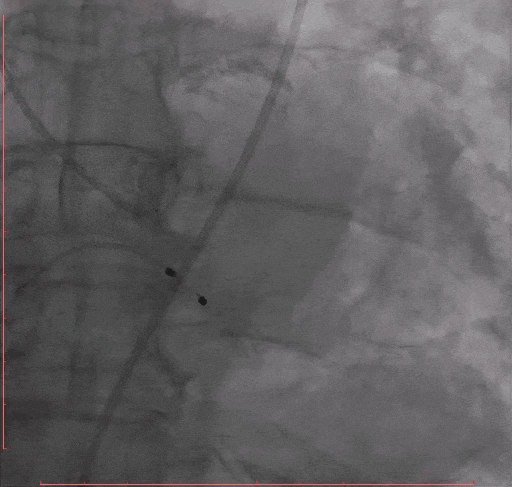

Step 2.冠脉造影

Step 3.导丝跨主动脉瓣后,干预冠脉病变,球囊无法通过LAD病变,予以旋磨